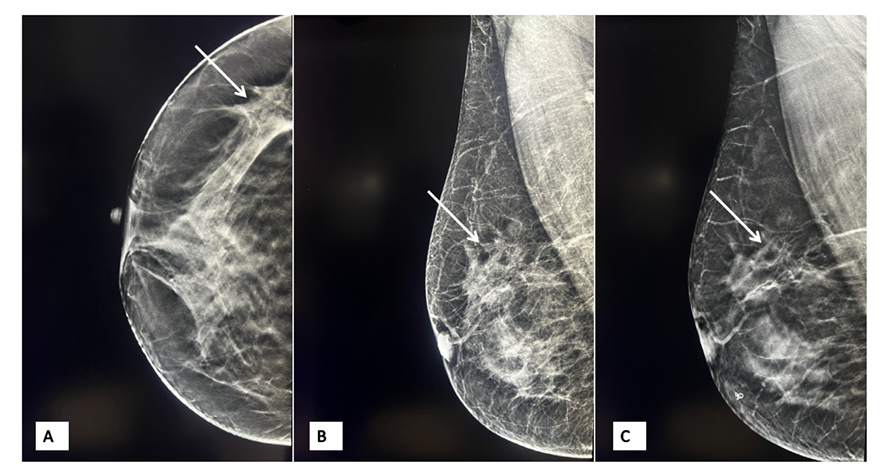

乳腺钼靶:右侧乳腺钼靶示外上象限轻微不对称及结构扭曲。

图3 右侧乳房钼靶